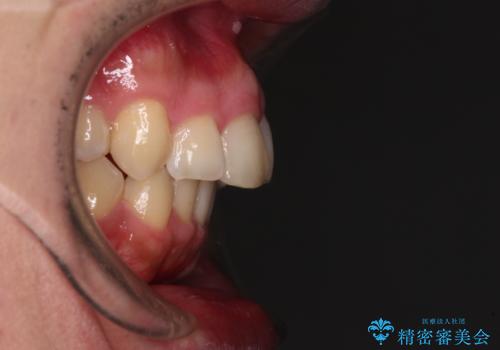

- 学生時代に抜歯矯正した歯列が後戻りしてきたとのことで来院された患者様です。

舌の突出癖が原因で上顎前歯が前方に移動したと考えられたため、舌のトレーニングを徹底して行っていただきながら、後戻りを解消していくこととしました。

ワイヤー矯正ということで、上顎大臼歯を後方に移動するための補助装置を併用して、積極的に前歯を引っ込めていくこととしました。